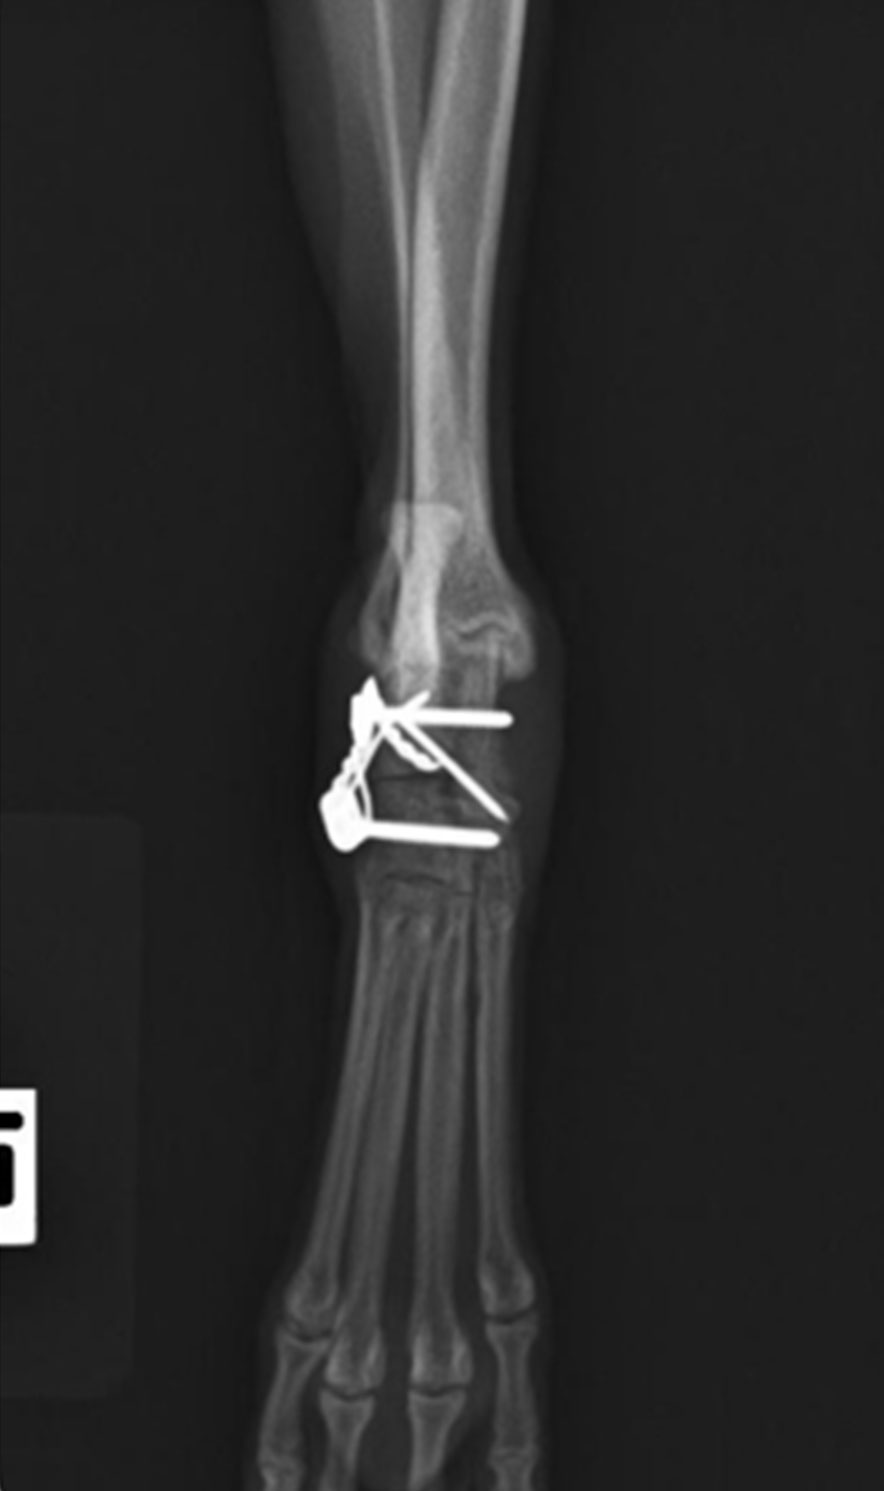

前肢の中手骨(手の甲の骨)を3本骨折した症例です。

直径0.6mmのピンを骨髄腔に入れて固定しております。

骨幅は2.5mm程度と細く、骨髄腔も狭いため、骨が破綻しないように慎重にピンの設置を行いました。

術前レントゲン検査 術後レントゲン検査